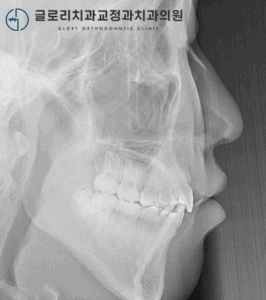

심한 돌출 및 반대교합, 하루라도 빨리 치료를 시작해야 되는 이유, 상봉동 치과 에서 알려드리겠습니다.

반갑습니다ㅎㅎ 김정은 원장입니다. ​ 저는 교정에 있어 치료 시기가 무엇보다 중요하다고 생각을 합니다. 연령에 따라 구강 상태와 주변 조직도 변화가 생길 수 있기 때문에 이점을 고려해서 계획을 세워야 되죠. ​…